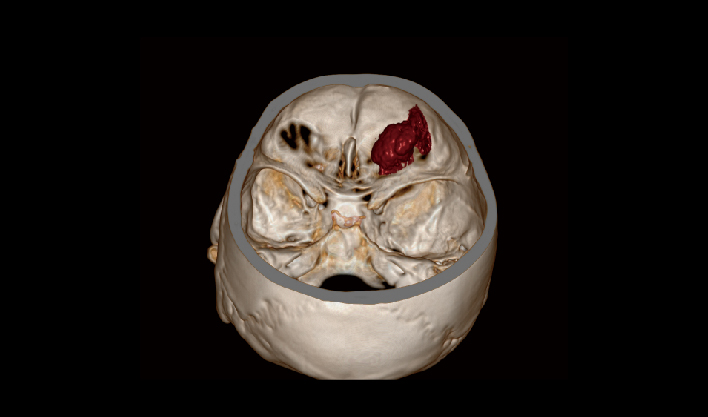

La matriz de reconstrucción de 1024*1024 amplía los datos de la imagen cuatro veces. Combinado con imágenes de corte fina, incluso las lesiones más invisibles son claramente visibles.